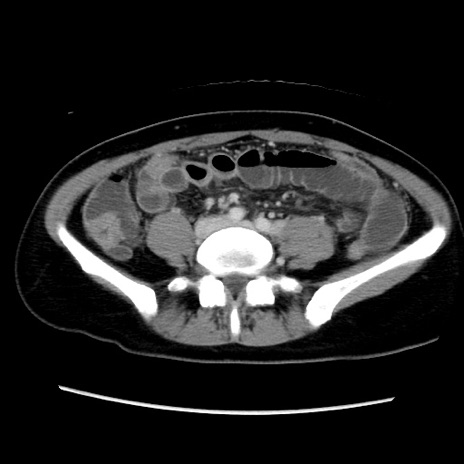

症例39(横断像)

【症例】40歳代女性

【主訴】上下腹部痛

【現病歴】2日目から下腹部痛あり。夜間は痛みで眠れなかった。昨日より上腹部痛と下痢が出現。臥位で痛みは軽快したため、休んでいた。本日になって臥位でも立位でも痛みが強くなってきたため救急要請。

【既往歴】子宮内膜症

【身体所見】部:平坦・軟、左上下腹部に圧痛あり、反跳痛あり。

【データ】WBC 21800、CRP 26.78